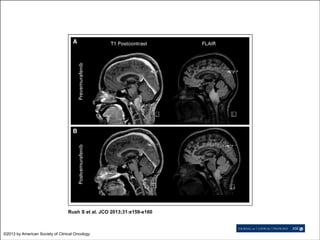

• Rush, JCO, 2013

- ganglioglioma de

tronco tratado com vemurafenibe

Imagens: Plexxikon

Rush S et al. JCO 2013;31:e159-e160

©2013 by American Society of Clinical Oncology

• Vemurafenibe (Zelboraf®) -uso adulto (FDA e ANVISA) • BRAF V600E • Melanoma metastático, irressecável, recorrente, refratário • Astrocitomas (até 30%) e gangliogliomas (>50%) • Korshunov, 2009 - fusão BRAFKIAA1549 e IDH1 diferenciam astrocitomas pilocíticos e difusos • Rush, JCO, 2013 - ganglioglioma de tronco tratado com vemurafenibe

Rush S etal. JCO 2013;31:e159-e160 ©2013 by American Society of Clinical Oncology